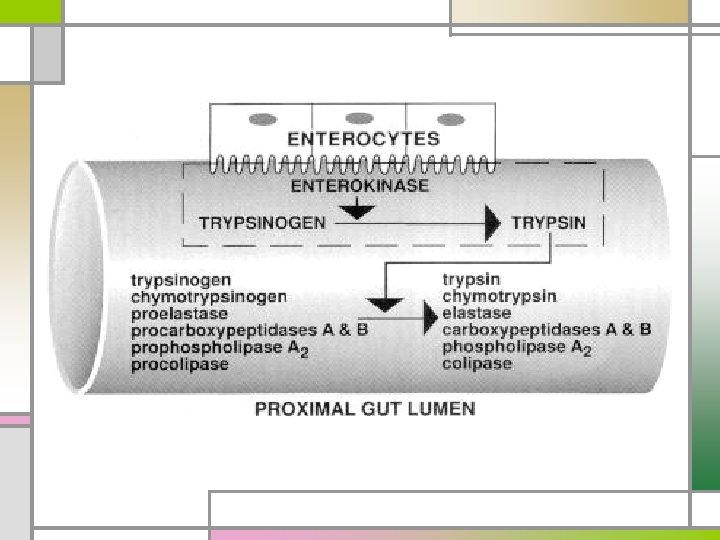

n Amylolytic enzymes – Amylase - starch to oligosaccharides or disaccharide Enzyme Excretion n Lipolytic enzymes - Lipase, phospholipase A, cholesterol-esterase n Proteolytic enzymes - Endopeptidase (trypsinogen, chymotrypsin) Cholecystokinin act on internal peptide bonds of proteins - Exopeptidase (carboxy or aminopeptidase) act on carboxyl-teminal and amino-terminal - Elastase Secreted as inactive precursors